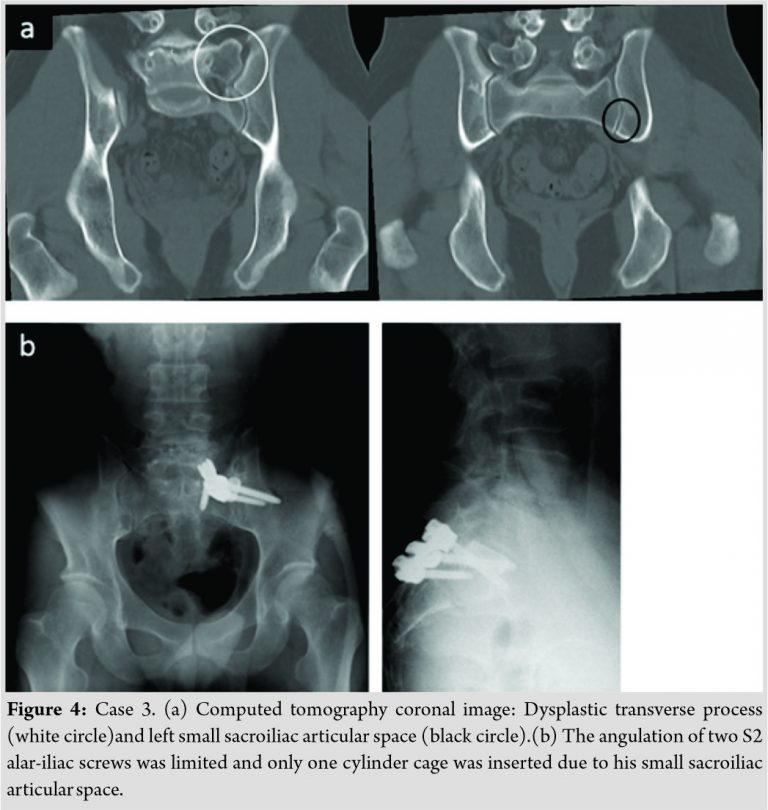

A 35-year-old man had the right SIJ pain and had LSTV Type Ib. A definitive diagnosis of SIJ pain was confirmed by SIJ injections. Conservative therapies performed for 8 months could not relieve his symptoms. We attempted to perform SIJ arthrodesis with the posterior approach using an S1 pedicle screw, two S2 alar-iliac screws, and two cylinder cages. In this anomaly, the sacrum was very small. The angulation of two S2 alar-iliac screws was limited due to the patient’s small sacroiliac articular space. When we connected the heads of the three screws (one S1 pedicle screw and two S2 alar-iliac screws) with the rod, the three screw heads were tightly touching each other due to the posterior narrow sacral space (Fig. 4). The S1 pedicle screw should have been inserted more cranially in this case when there was a lack of space to insert the other two screws. For this patient, only one cylinder cage could be inserted in the joint.

We have experienced all approaches for SIJ arthrodesis in the past 20 years (Fig. 5). In surgical procedures of anterior SIJ arthrodesis, the psoas major muscle is retracted medially to attach a plate and to insert screws on the sacrum side [6]. In LSTV Type Ⅳ in our series, most cranial sacrum foramen was larger and irregularly round, and the nerve root ran to the lateral side from the deformed foramen more than usual. The psoas major muscle should be retracted gently to attach a plate in patients with this kind of anomaly. In LSTV Types Ⅱ, Ⅲ and Ⅳ surgeons should know the risk of nerve injury due to the nerve running changes from a deformed sacrum foramen if they use the anterior approach. Particularly, in Types Ⅱ and Ⅳ, most cranial sacrum foramen tends to be larger and irregularly round on the diarthrodial side. When we use the posterolateral approach for SIJ arthrodesis with multi screws or triangular titanium implants [3], we should pay attention to prevent the screw/implant from penetrating the anterior margin of the sacrum. For this purpose, intraoperative C-arm imaging which included a pelvic inlet view, outlet view, and lateral view was crucial. Particularly, it was important to prevent screws from being inserted toward the pelvic cavity by checking that the tip of the screw did not penetrate the anterior margin of the sacrum in the inlet view. In our Case 2, however, the most cranial screw penetrated the anterior margin of the sacrum, which caused S1 radiculopathy. As the cranial sacral body (sacral alar) could be thinner than usual when the patients had any type of LSTV except for Type Ⅰ, the inlet view is not enough to insert the most cranial screw safely. In such situation, the lateral pelvic view is more credible [7]. Pre-surgical planning to determine the implant insertion point is necessary based on the CT image, particularly in the sagittal plane. Intraoperative CT imaging and navigation may reduce the risk of screw malposition in patients with sacral dysmorphism [8]. Regarding the posterior SIJ arthrodesis using S1 pedicle screw and S2 alar-iliac screws, we had technical difficulty when the patient had a small sacrum induced by LSTV Type I. Regretfully, in this study, it was unclear whether patients with LSTV had sacralization of L5 or lumbarization of S1 because CTs or MRIs for the whole spine were not performed. However, regardless of inaccurate identification of the spinal segment, the sacrum becomes small when the S1 vertebra seems to change toward the lumbar vertebra. Therefore, the S1 pedicle screw should insert more cranially than usual for the insertion of two S2 alar-iliac screws and two cylinder cages could not be put into the SI joint space.